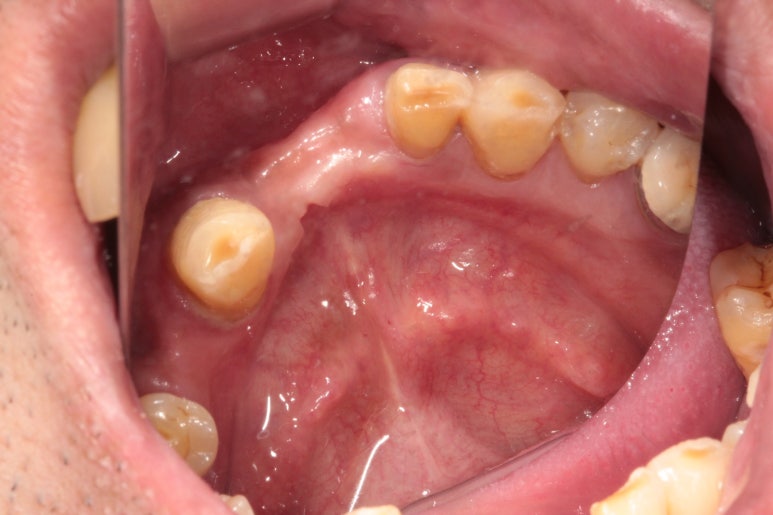

아래 앞니도 상당히 좁아져버린 잇몸뼈의 모양을 관찰하실 수 있을거에요.

이런 부위는 임플란트를 심어내기에도 어려워져 버린답니다.

심해진 만성치주염으로 인해 위 앞니들은 제 자리를 잃어버렸습니다.

치아 사이 간격이 커지기도 하고, 정출되는 등 병적 치아이동 (pathologic migration)을 겪게 되지요.